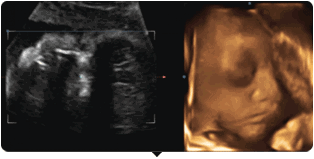

四维彩超就是四维成像技术(4D),能直观,立体显示人体器官的三维结构及动态、实时地观察立体结构。主要可以进行胎龄检测、分析胎儿的发育情况、筛查胎儿畸形等。

单胎为怀孕第20—28周,双胞胎为18-22周。因为这个时期的胎儿大小适中,羊水量充足,比较容易采集到相对清晰的图像。

四维彩超动图欣赏

甘谷四维彩超,骨密度检测,清晰度高,显示准确,受到了患者的一致好评。

四维彩色超声诊断仪出色的人体工程学设计,不存在射线、光波和电磁波等方面的辐射,对人体的健康没有任何影响。